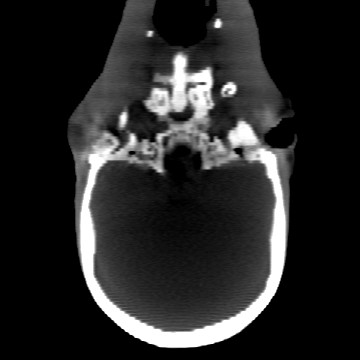

Cone-beam CT (CBCT) employs a flat-panel detector to achieve three-dimensional imaging with high spatial resolution. However, CBCT is susceptible to scatter during data acquisition, which introduces CT value bias and reduced tissue contrast in the reconstructed images, ultimately degrading diagnostic accuracy. To address this issue, we propose a deep learning-based scatter artifact correction method inspired by physical prior knowledge. Leveraging the fact that the observed point scatter probability density distribution exhibits rotational symmetry in the projection domain. The method uses Gaussian Radial Basis Functions (RBF) to model the point scatter function and embeds it into the Kolmogorov-Arnold Networks (KAN) layer, which provides efficient nonlinear mapping capabilities for learning high-dimensional scatter features. By incorporating the physical characteristics of the scattered photon distribution together with the complex function mapping capacity of KAN, the model improves its ability to accurately represent scatter. The effectiveness of the method is validated through both synthetic and real-scan experiments. Experimental results show that the model can effectively correct the scatter artifacts in the reconstructed images and is superior to the current methods in terms of quantitative metrics.